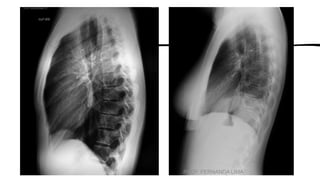

A anatomia radiográfica do tórax é divida em três seções:

•caixa torácica,

•sistema respiratório

•mediastino.

Sistema respiratório - A respiração consiste na troca de substâncias

gasosas entre o ar que respiramos e a corrente sanguínea.

• Faringe

• Traqueia

• Brônquios; Bronquíolos; Alvéolos

• Pulmões.

• Diafragma formato de cúpula,

músculo primário da inspiração.

• Cada metade do diafragma denomina-

se hemicúpula; hemidiafragma.

(“hemi” significa metade).

Mediastino -

A porção mediana da cavidade torácica, localizada entre os pulmões, é denominada mediastino.